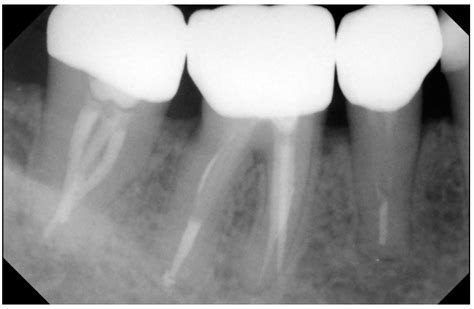

• Endodontic Procedures: In root canal treatments, Crown X Ray Dental technology aids in identifying the exact location and extent of the infection, ensuring that the procedure is performed accurately.

• Periodontal Disease: Crown X Ray Dental technology helps in diagnosing and monitoring periodontal disease by providing a clear view of the bone and gum tissues.